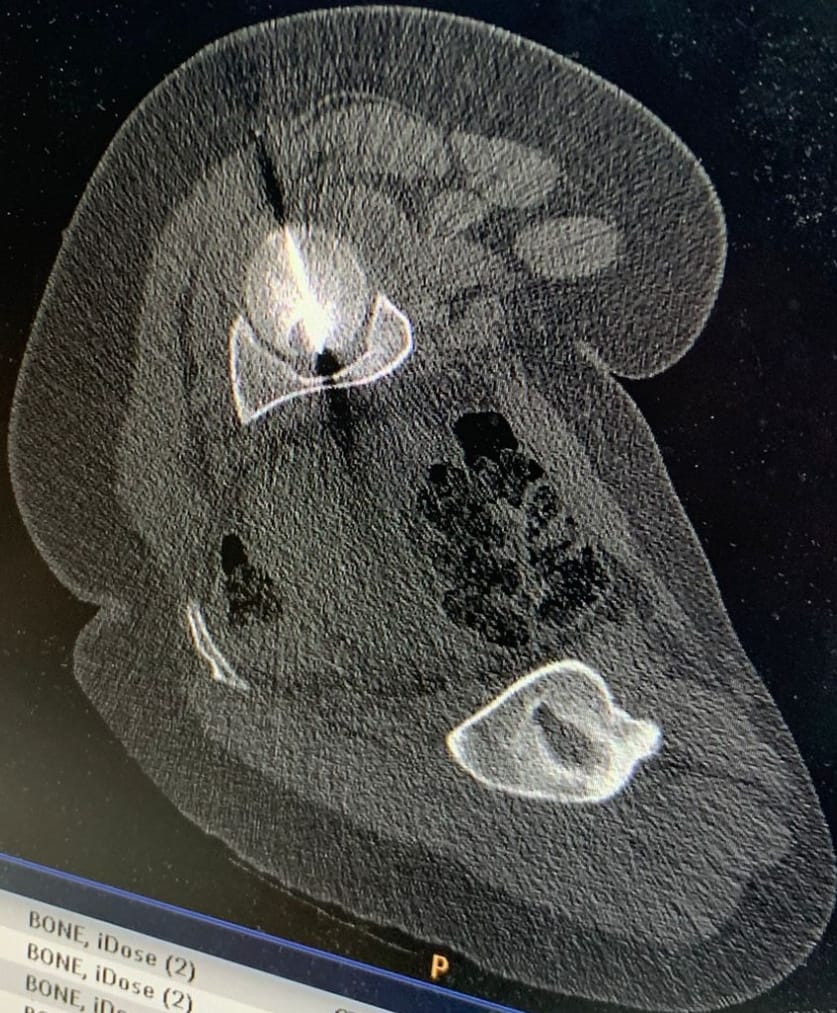

وبيّن البطوش، أنّ الفريق الطبي نجح في الوصول إلى مركز الورم بدقة عالية باستخدام تقنيّة التصوير الطبقيّ المحوريّ (CT Scan)، تلا ذلك إجراء الكي بالتقنيّة الحراريّة باستخدام المايكروويف (Microwave Ablation)، وهي من أحدث التقنيّات العالميّة في علاج أورام العظام دون الحاجة إلى التدخّل الجراحيّ المفتوح.